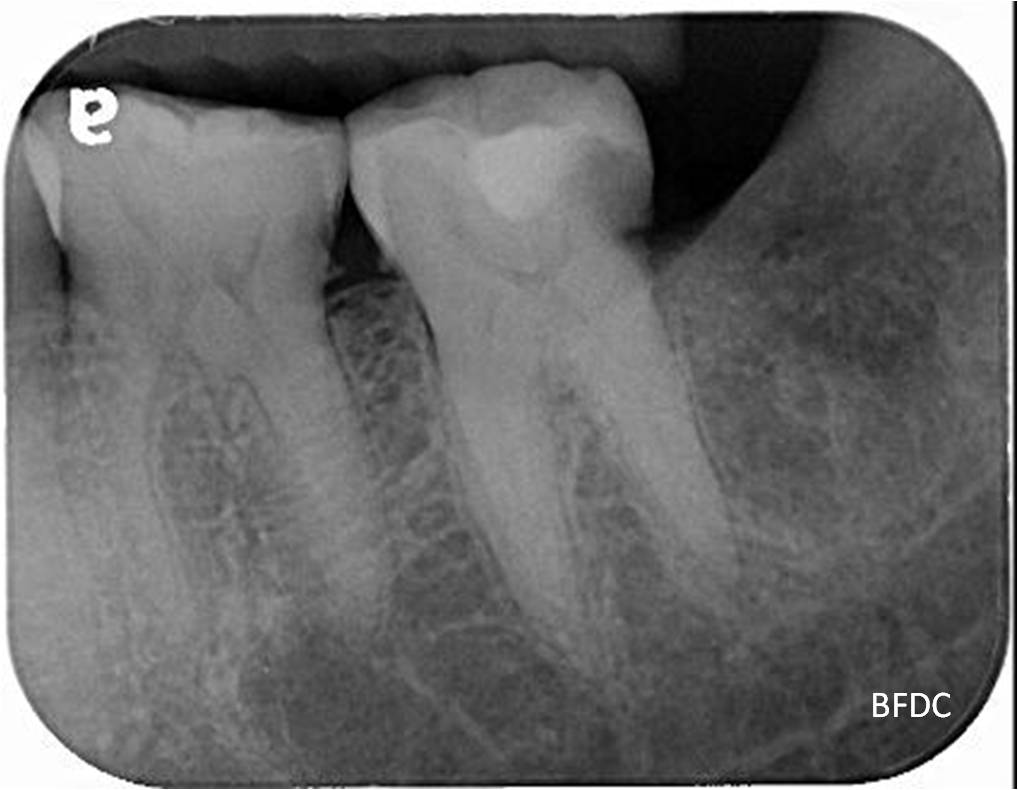

治療後,骨缺損修復

術前、術後比較